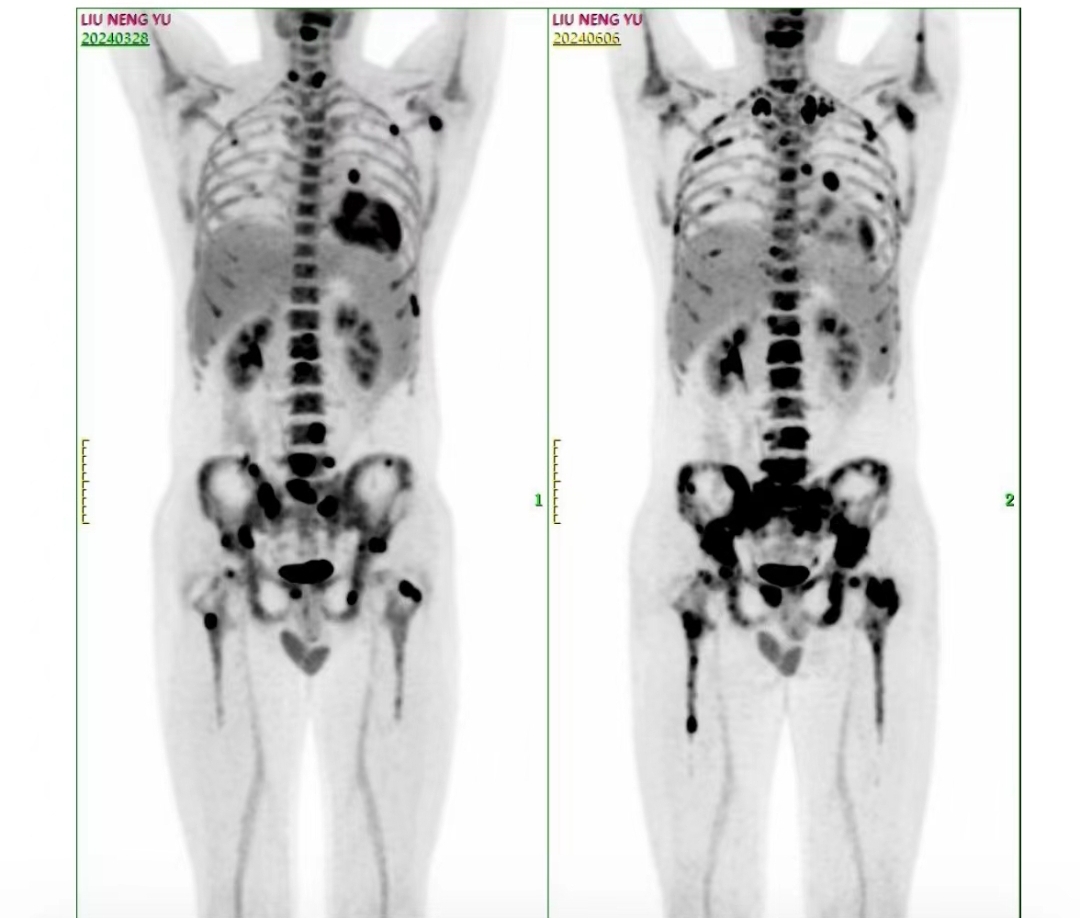

4疗后进展了 霍奇金

这做的abvd之后又进展了 怎么办啊 急死人了

确实进展了,需要重新定方案了,祝福好运